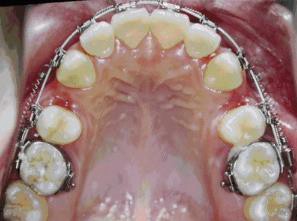

有的患者認(rèn)為拔了牙,牙齒缺失后,會(huì)出現(xiàn)牙齒松動(dòng)的現(xiàn)象。德倫口腔矯治專家指出,對(duì)于一些錯(cuò)合畸形,拔牙是必要的治療手段,例如牙齒嚴(yán)重?fù)頂D,需要拔除相對(duì)不重要的牙齒(譬如第一雙尖牙),利用拔牙空出的間隙,才能把擁擠的牙齒排整齊;嚴(yán)重前突的牙齒,例如大齙牙等,通過(guò)正畸可將牙齒往里收,需要利用拔牙后的間隙才能更好地改善面型。

360截圖20170120173126256.jpg

▲紅圈所示,牙合面有兩個(gè)尖叫做雙尖牙

360截圖20170120173136868.jpg

▲嚴(yán)重的牙列擁擠或齙牙,一般都需要拔牙矯正